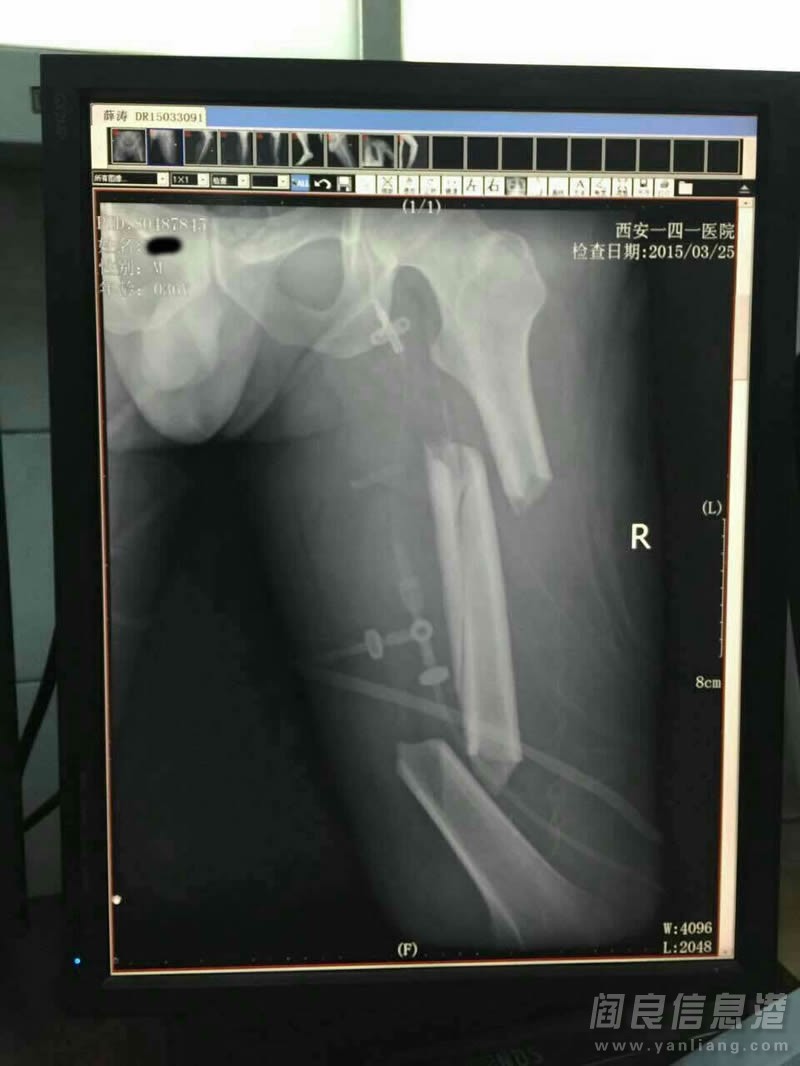

3.25宝马被撞当事人脾脏已经摘除,全身多处严重性骨折